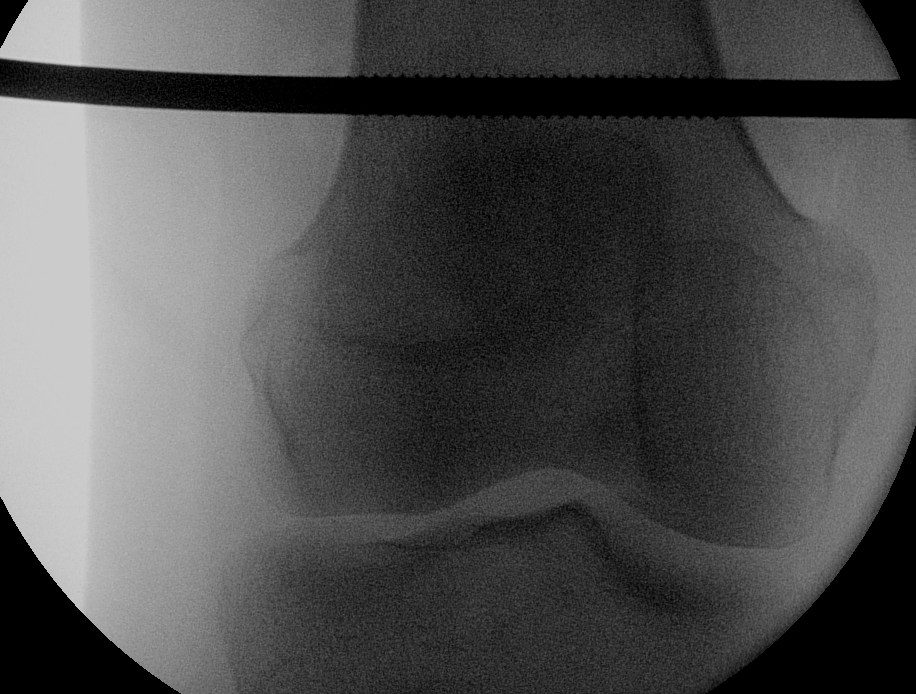

Insertion Femoral Steinman Pin

Indications

- displaced acetabular fracture

Technique

- above blummenstaat's line

- in metaphyseal bone

- minimum 10 pounds weight, may need more

- assess post operative reduction